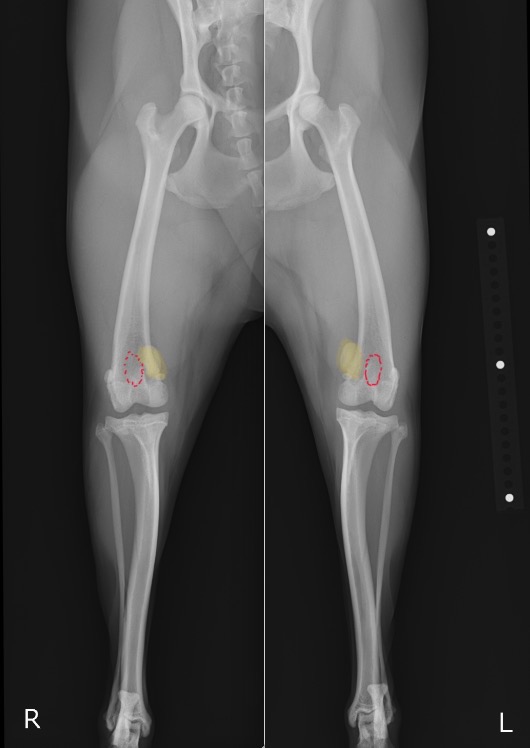

X線を見ると、膝蓋骨が本来あるべき位置(赤点線)から内側に脱臼してしまっていることが分かります。(黄色)

整形外科学的検査とX線検査により、左右共に膝蓋骨内方脱臼のGrade3と診断しました。

重症度としては4段階中3番目であり、日常的に脱臼している状態と推察されました。